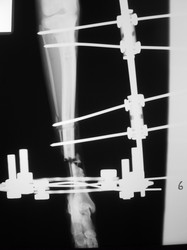

Fijación Externa

PRÁCTICAS CURSO DE FIJACIÓN EXTERNA PERFECCIONAMIENTO.

Híbrido.